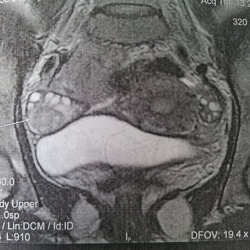

04.12.2011 - 18:56

УЗИ - T-r правой почки.